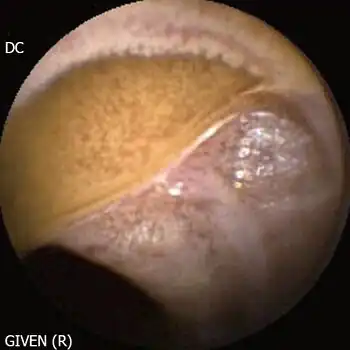

| Hypobetalipoproteinemia, endoscopic picture is characterized by a diffuse whitish pattern of the mucosa due to the accumulation of fat vesicles in the enterocytes | |